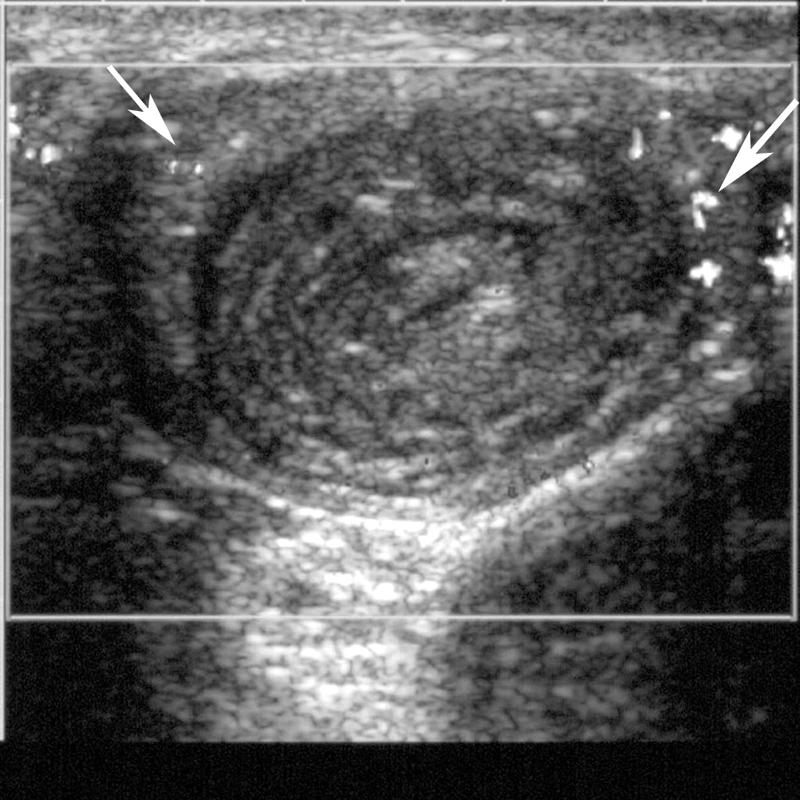

rectal bleeding

Intussception

vomiting

abdominal pain

rectal bleeding

Intussception